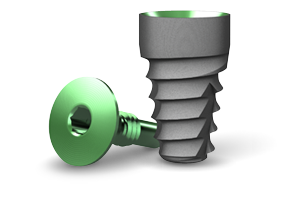

- Faster osseointegration with Laser-Lok technology across

entire implant surface41 - Excellent primary stability from tapered body

- Maximum surface area from power thread design

- Ideal for anatomically challenging conditions

- Wide array of restorative options

body-type

connection

placement

tapered

internal hex

bone level

Laser-Lok body

mount-free

4.5mm | 5.7mm

4.6mm | 5.8mm

7.5mm | 9mm